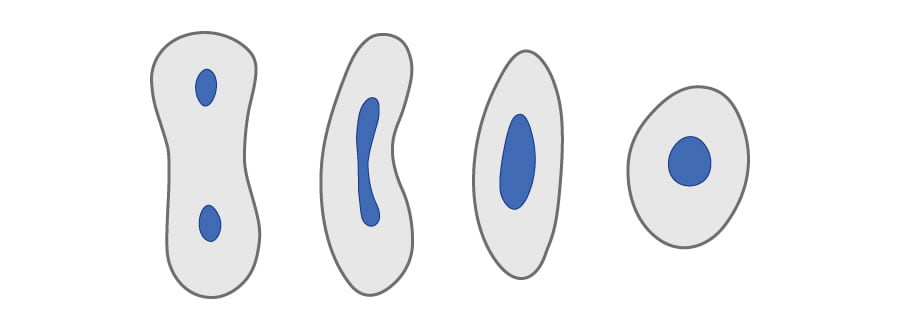

Peripheral reinforcement

71% more resistant to deformation before fracture*

- Peripheral reinforcement with the Biolight® DRILL-FREE multi-post system offers a superior resistance to mechanical stresses, when compared to a central post.

- Traditional engineering reinforcement concepts have long-established a reliance on peripheral over central reinforcement.

*Based on internal comparative engineering data.